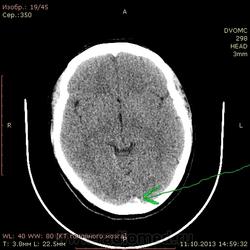

42 года. Слева в лобной доле кровоизлияние в 2011 году. Это понятно.

Есть другой вопрос нормальное ли обызвествление в затылочной доле?

А это не синус?

Может обызвествление твердой мозговой облочки.